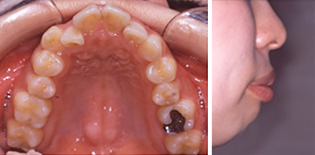

治療前-治療後

歯を抜いても歯並びが狭く小さくならないように治療します。

上顎の真ん中にあった骨隆起という、余分な力がかかるとできるでっぱりがなくなってきました。

歯並びの幅が広がって、きれいなU字型になってきました。これが本来の歯列の形です。

引っ込んでいた下顎が自然に前に出て、きれいな横顔になりました。